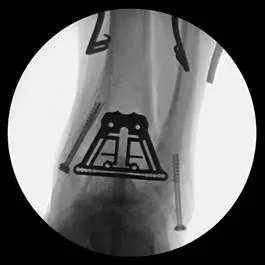

This is a pic of the implant getting mapped out for placement in the distal tibia

This is the guide for the tibia component of the implant